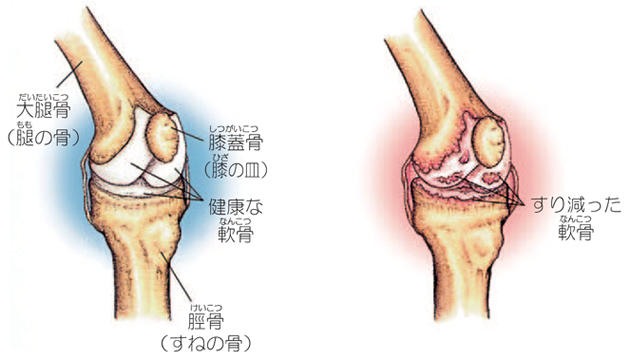

膝関節は、大腿骨、脛骨、膝蓋骨からなる関節です。関節の表面は軟骨で覆われ、膝関節のスムーズな動きを可能にしています。加齢や外傷などにより軟骨が減少すると、すり減った軟骨の下のむき出しになった骨同士がこすれ合い、炎症が生じ痛みを感じます。

軟骨の減少により膝関節の痛みが生じる疾患を変形性膝関節症と呼びます。本邦における変形性膝関節症の患者数は約1000万人とも言われ、多くの方がお悩みの疾患です。歩行中や階段昇降時の痛みや、正座ができないなどの症状が生じます。

すり減った大腿骨頭の軟骨